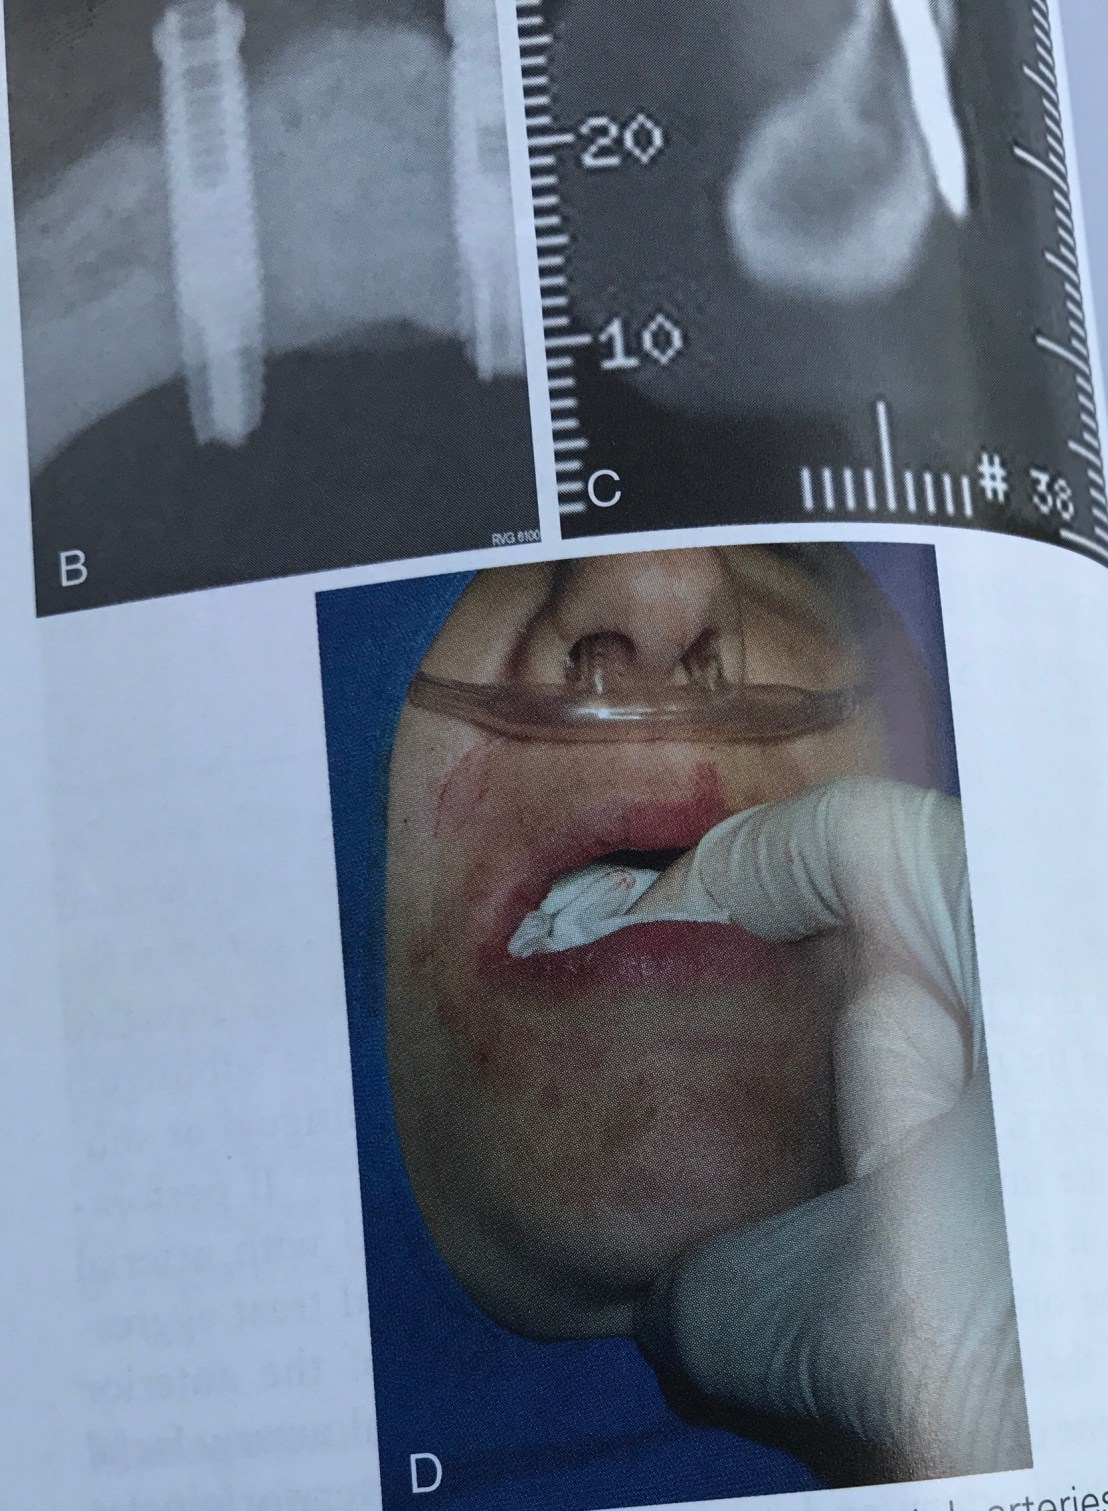

อันนี้ผมเพิ่งเคยเห็น น่ากลัวมาก คือ ฝังไปโดน Sublingual artery ครับ

อันตรายของมันคือ เกิด Sublingual hematoma ไป obstruct Airway

สังเกตฟิลม์ OPG ระดับ Implant อยู่ต่ำกว่า CEJ ของฟันข้างเคียงมาก ปลายของ Implant จึงทะลุ Lingual plate ไปโดน Artery

ในรูป D การใช้ Forceps ดึงลิ้นคนไข้ออกมาเพื่อ stop bleed และเปิด Airway รอทีม EMS มาถึงครับ

รูป Gross แสดง Artery ที่เกี่ยวข้อง และ Film แสดงการ Perforate ชัดเจน

รูป D แสดงการใช้ Bimanual pressure เพื่อหยุด bleed โดยใช้นิ้วชี้กด Gauze ใต้ลิ้นและนิ้วโป้งกดจาก Extra-oral บริเวณใต้คางในทิศดันขี้น